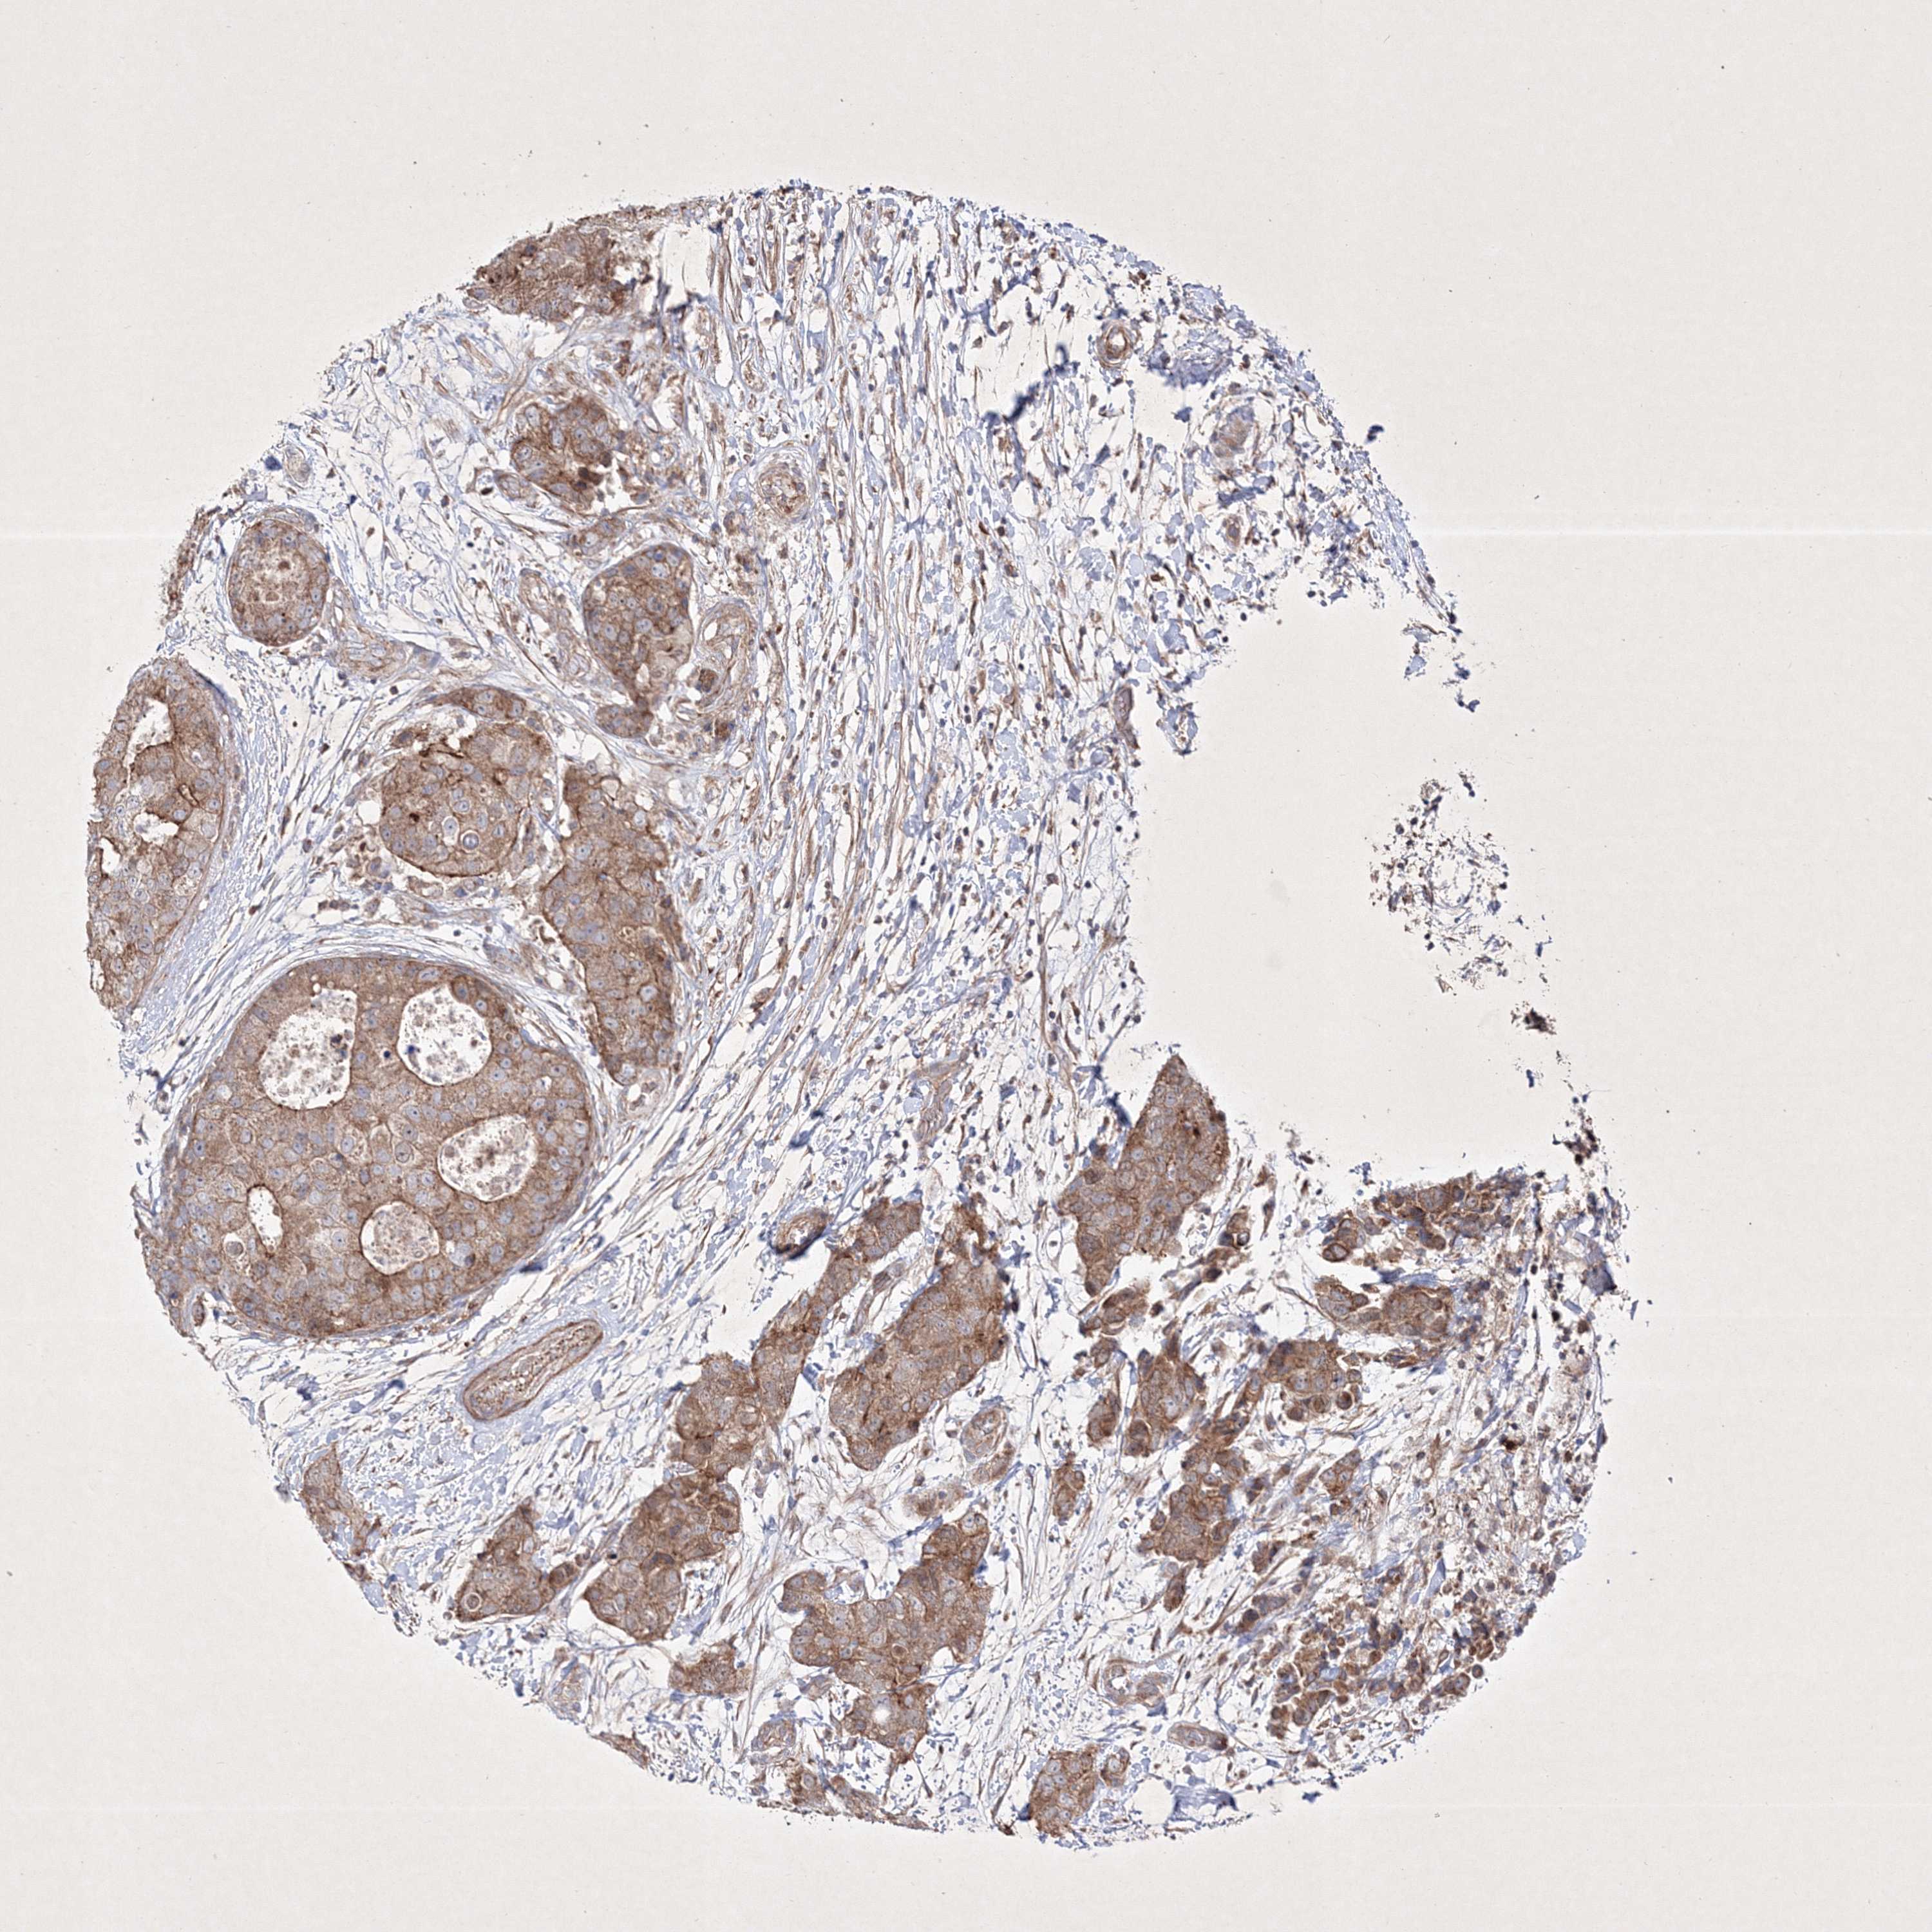

CANCER BREAST CANCER Show tissue menu

BRCA TCGA BRCA VALIDATION PROTEIN EXPRESSION

ANTIBODIES

AND

VALIDATION